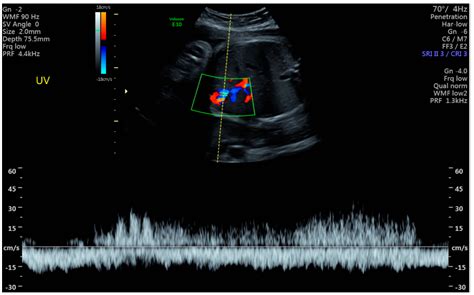

Detection usually occurs during the second or third-trimester anatomy scan. Sonographers look for a fluid-filled, cyst-like structure within the fetal abdomen that shows blood flow when color Doppler ultrasound is applied. Because the structure is vascular, it is easily distinguishable from other fluid-filled cysts (like those in the gallbladder or bowel) once the appropriate imaging techniques are utilized.

• Doppler Flow Studies: These studies measure the velocity and pattern of blood flow through the varix to check for turbulence or restricted flow.